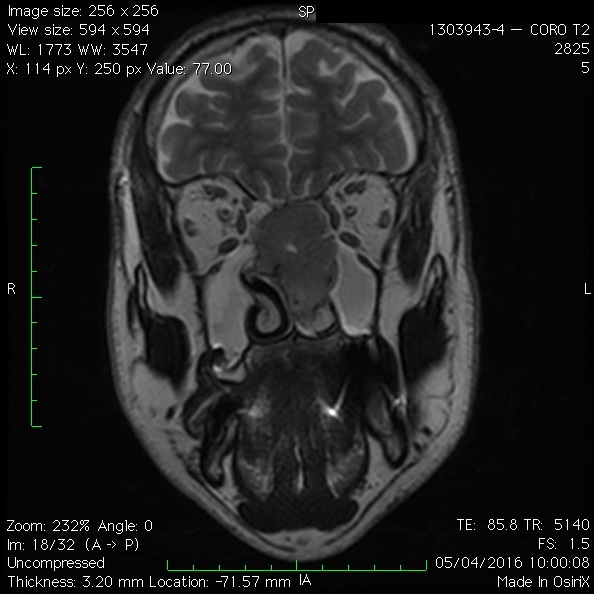

Au niveau de la base du crâne il prend souvent naissance dans l’ethmoïde, plus précisément dans la fente olfactive et est alors appelé « adénocarcome de l’ethmoide ». C’est une tumeur retrouvée classiquement chez les travailleurs du bois (ébénistes, parquetiers…) exposés de longues années aux poussières de bois. Il s’agit alors d’une maladie professionnelle.

Une chirurgie minimale invasive endoscopique de la base du crâne peut souvent être utilisée, ce qui contribue à réduire les effets secondaires et le risque d’infection et accélère la guérison. Certains patients nécessitent également une radiothérapie ou une chimiothérapie. À l’aide de technologies de pointe et de dispositifs d’imagerie, les rayonnements peuvent cibler précisément les tumeurs des adénocarcinomes tout en épargnant les tissus sains et les organes environnants.

Voir une vidéo de l’intervention